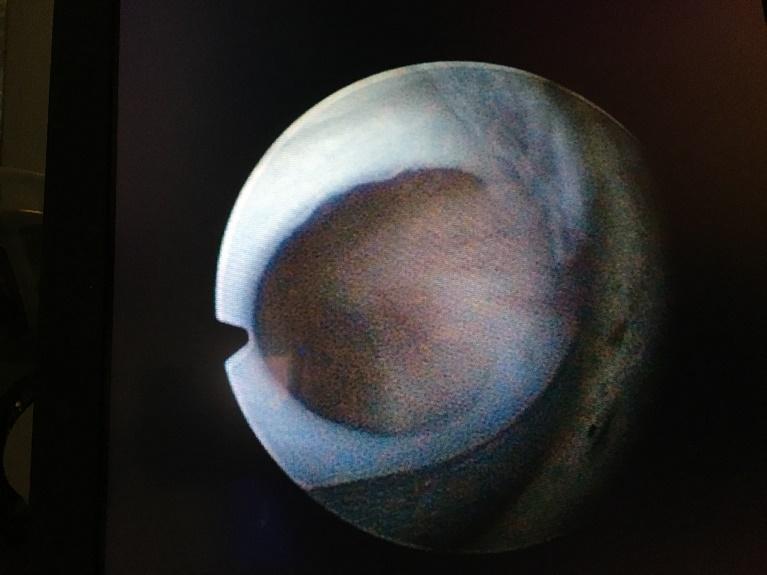

Beeld van urethrakleppen bij de kijkoperatie (cystoscopie). De vliezen zitten vast aan de boden en zijwand van de plasbuis en zijn aan het “plafond” van de plasbuis samengegroeid.